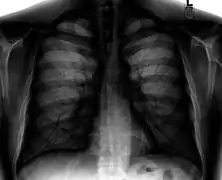

Different views (also known as projections) of the chest can be obtained by changing the relative orientation of the body and the direction of the x-ray beam. The most common views are posteroanterior, anteroposterior, and lateral. In a posteroanterior (PA) view, the x-ray source is positioned so that the x-ray beam enters through the posterior (back) aspect of the chest and exits out of the anterior (front) aspect, where the beam is detected. To obtain this view, the patient stands facing a flat surface behind which is an x-ray detector. A radiation source is positioned behind the patient at a standard distance (most often 6 feet, 1,8m), and the x-ray beam is fired toward the patient.

Typical views

Required projections can vary by country and hospital, although an erect posteroanterior (PA) projection is typically the first preference. If this is not possible, then an anteroposterior view will be taken. Further imaging depends on local protocols which is dependent on the hospital protocols, the availability of other imaging modalities and the preference of the image interpreter. In the UK, the standard chest radiography protocol is to take an erect posteroanterior view only and a lateral one only on request by a radiologist.[5] In the US, chest radiography includes a PA and Lateral with the patient standing or sitting up. Special projections include an AP in cases where the image needs to be obtained stat (immediately) and with a portable device, particularly when a patient cannot be safely positioned upright. Lateral decubitus may be used for visualization of air-fluid levels if an upright image cannot be obtained. Anteroposterior (AP) Axial Lordotic projects the clavicles above the lung fields, allowing better visualization of the apices (which is extremely useful when looking for evidence of primary tuberculosis).